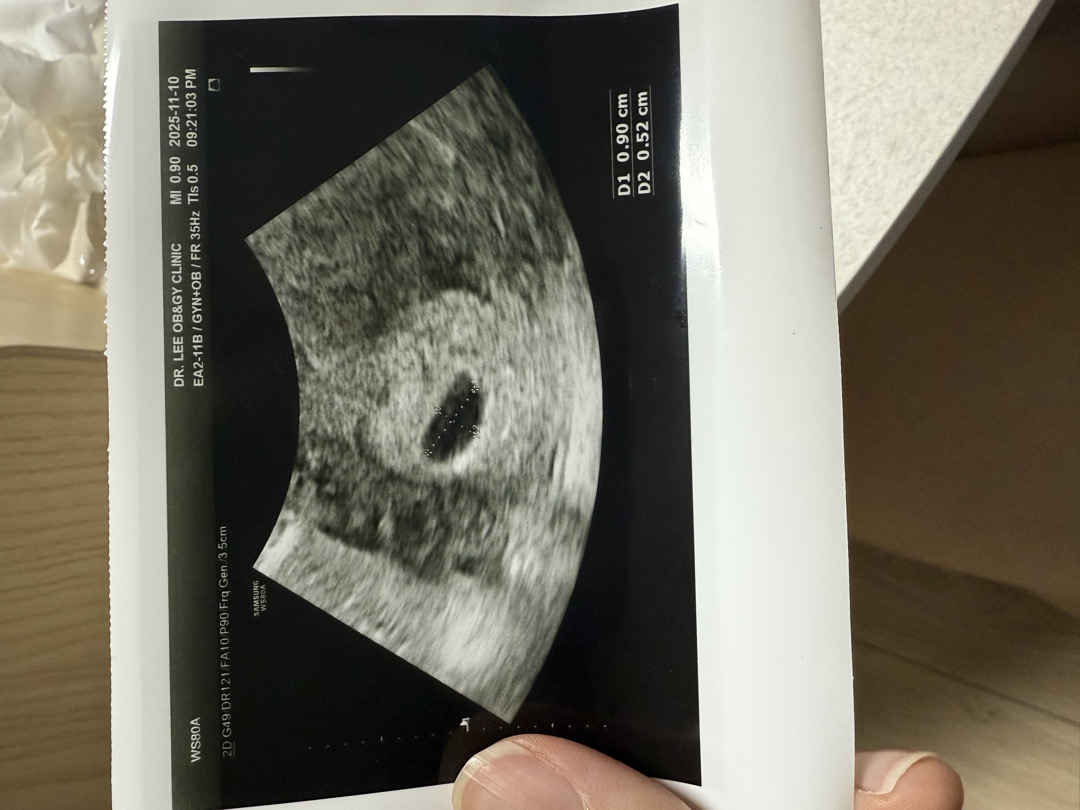

11/6일에 확인한 초음파사진에는 아기집이 0.72cm 입니다 5주차 인거같다고하셨습니다 근데 11/10일 오늘 5주 4일차인데 다른병원에서 확인한 초음파 사진에 0.90cm 이라 되어있는데 의사선생님은 아기집 크기가 똑같다면서 자연유산 가능성이 높다고 하는데 솔직히 4일전에 괜찮다하다가 제눈에는 아기집도 조금이지만 커지기도하고 비슷한 사진이 왜 자연유산이라는건지 이해가 잘안갑니다.. 제초음파 사진좀 봐주실수있나요?